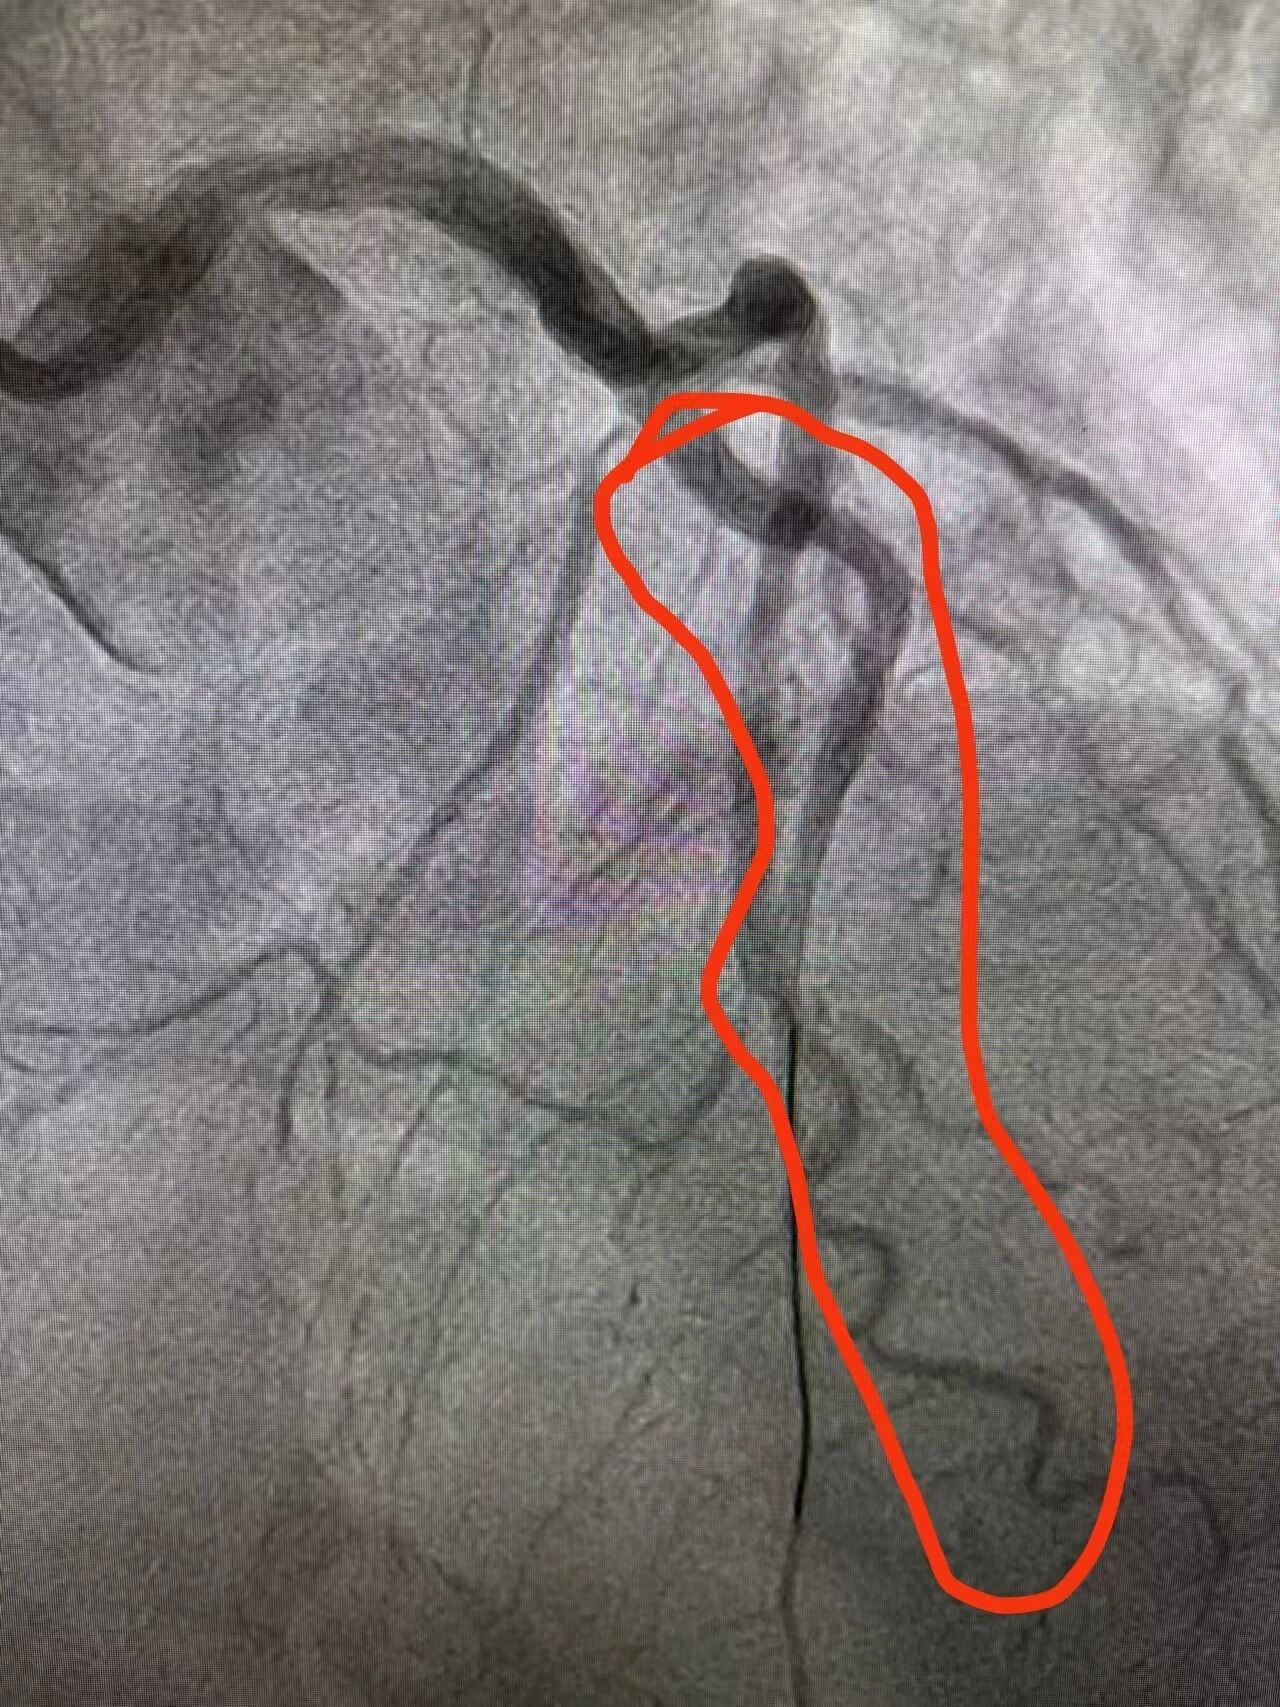

当林先生推入导管室时,手术器械、设备参数早已调试就绪。造影、球囊扩张、支架植入…… 一系列操作行云流水,堵塞的前降支血管成功开通,心肌供血瞬间恢复。